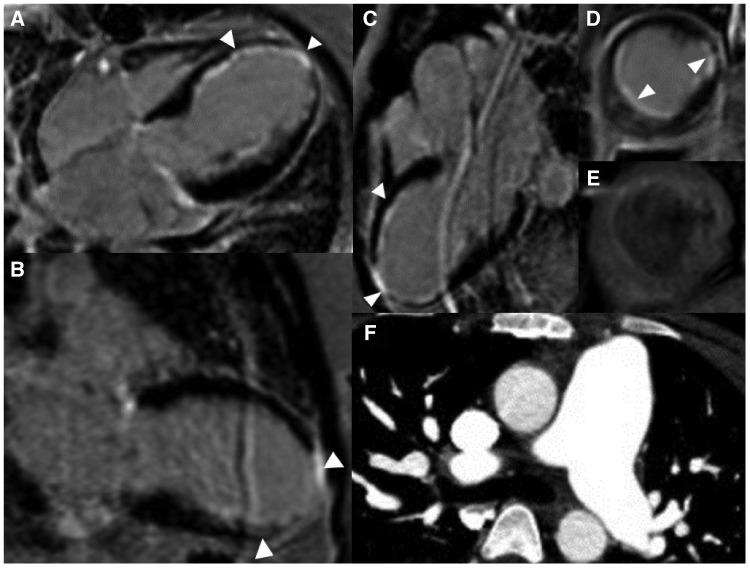

A 23-year-old woman with SLE presented with typical angina and worsening dyspnoea on exertion. Coronary angiography revealed severe triple vessel disease with a 'string of beads' appearance classic for coronary vasculitis. Transthoracic echocardiogram revealed ejection fraction of 25-30% with a severely hypokinetic distal septum and distal anterior wall and an akinetic apical wall. Despite vasculitis treatment with cyclophosphamide and pulse-dose steroids, her coronary vasculitis did not improve. She was refractory to anti-anginal and guideline-directed medical therapy for heart failure and successfully underwent orthotopic heart transplant (OHT).

一名23岁的SLE女性患者出现典型心绞痛,且运动时呼吸困难加重。冠状动脉造影显示严重的三支血管病变,呈现出冠状动脉血管炎典型的“串珠样”外观。经胸超声心动图显示射血分数为25%-30%,室间隔远端、前壁远端严重运动减弱,心尖壁运动消失。尽管使用环磷酰胺和冲击剂量类固醇进行血管炎治疗,但其冠状动脉血管炎并未改善。她对抗心绞痛及针对心力衰竭的指南指导药物治疗无效,最终成功接受了原位心脏移植(OHT)。